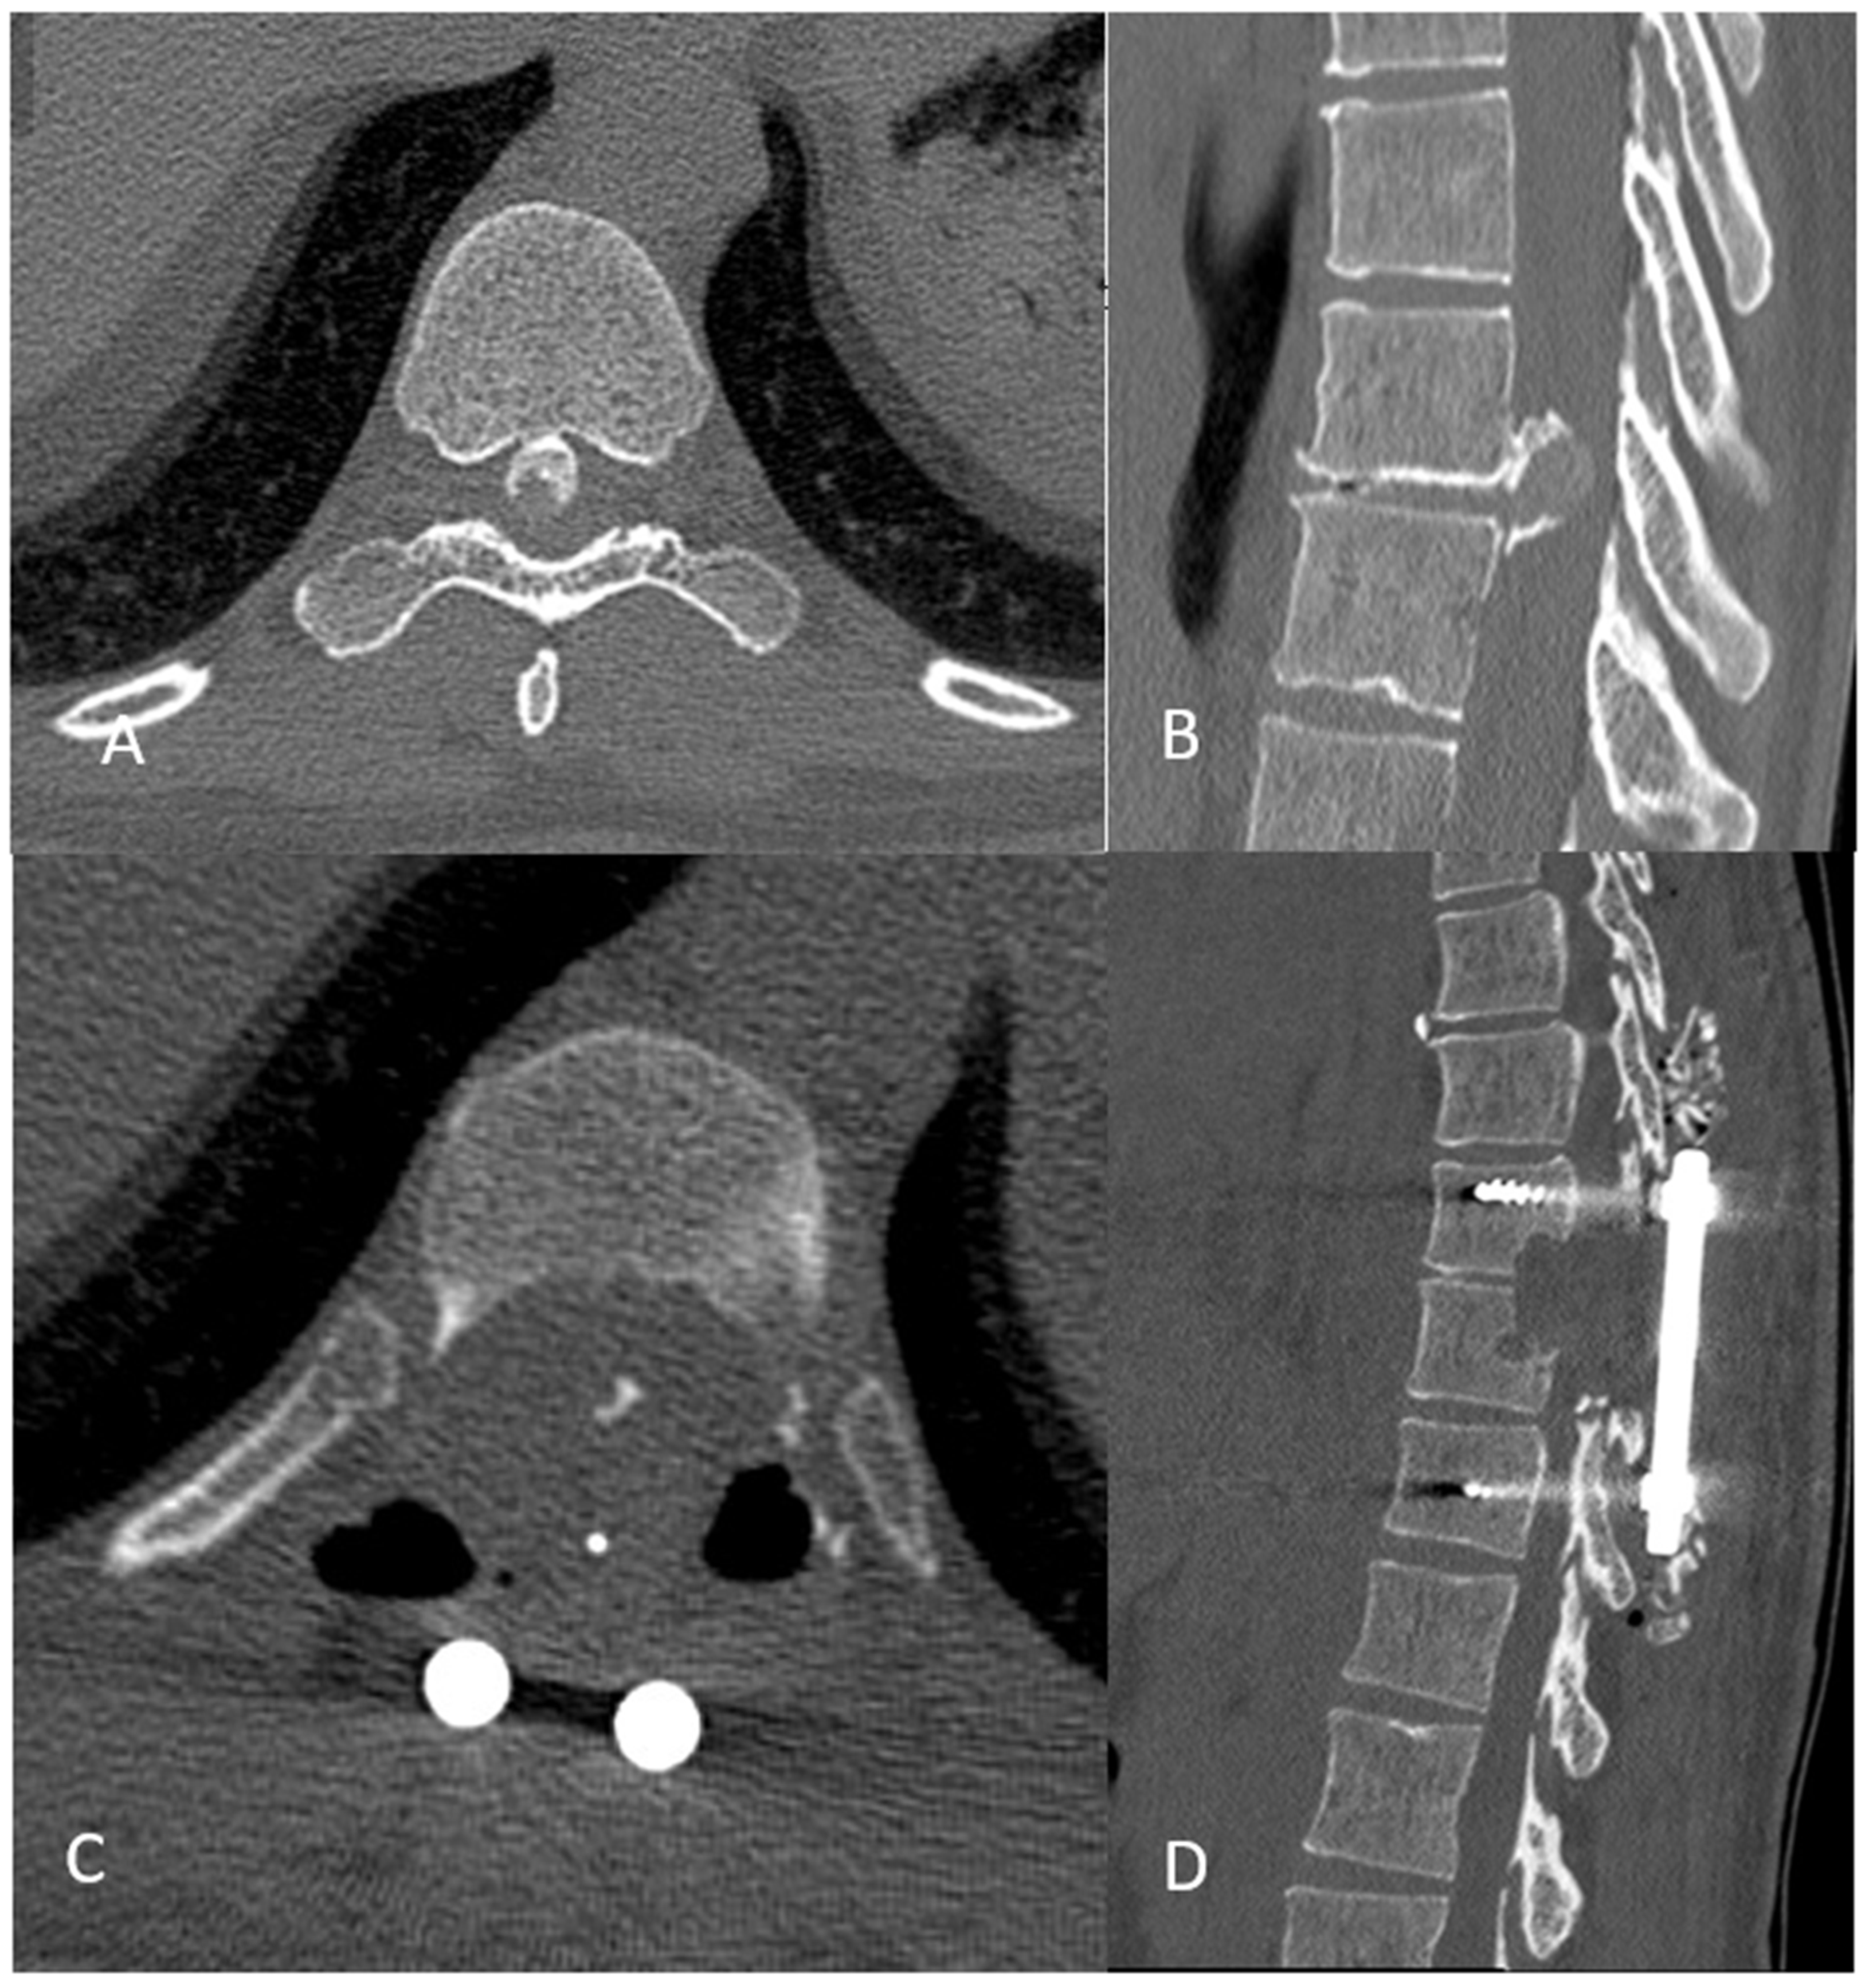

Resection of Calcified and Giant Thoracic Disc Herniation Through Bilateral Postero-Lateral Approach and 360° Cord Release: A Technical Note

- Preoperative screening with a good MRI and CT scan is crucial to determine the degree of calcification and the precise location of the cord inside the canal and its relation with the TDH.

- In the case of giant calcified TDH, a total release of the cord, 360°, is essential to remove all bony surrounding structures and reduce the risk of injury by pushing the cord against the contralateral pedicle.